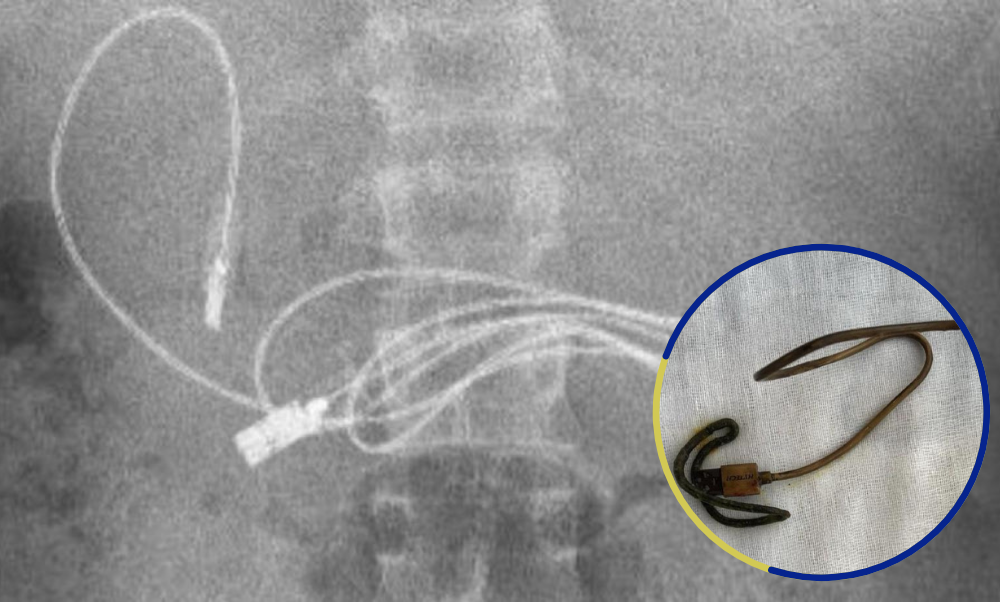

El menor señaló a los doctores que presentaba dolor y náuseas. Cuando los médicos observaron las imágenes de su torso, se dieron cuenta que en su estómago se alojaba un cable para cargador USB. Po lo que de inmediato procedieron a trasladarlo al Hospital de Firat en Elazig, donde se le hizo un procedimiento para retirar el objeto recubierto de plástico, informó The Mirrow.

El gastroenterólogo pediátrico Yasar Dogan fue el encargado de realizar la cirugía y compartió a través de sus redes sociales las imágenes que dan cuenta de la situación que presentaba el adolescente. El procedimiento consistió en hacer una endoscopía para retirar el objeto, sin embargo al retirarlo, también encontraron una banda elástica para el cabello junto al cable.

“Obviamente, tuvimos dificultades para quitar el cable, ya que un extremo había pasado al intestino delgado (…) Después de que el procedimiento concluyó con éxito, el paciente fue enviado a casa con buena salud”, expresó el doctor Yasar Dogan a través de sus redes sociales.